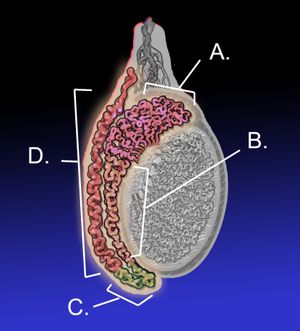

부고환염은 부고환의 염증으로, 주로 16세에서 30세 사이의 남성에게서 발생한다. 급성 부고환염의 가장 흔한 원인은 세균 감염이며, 성적으로 활동적인 남성의 경우 클라미디아 트라코마티스가 주요 원인이다. 비감염성 원인으로는 무균 뇨의 역류, 소아의 바이러스 감염, 사르코이드증 등이 있다. 증상으로는 음낭의 통증과 부종, 발열 등이 나타나며, 고환 염전과 감별이 필요하다. 진단은 증상과 도플러 초음파 검사를 통해 이루어지며, 치료는 항생제 투여가 일반적이다. 합병증으로는 농양, 불임, 만성 통증 등이 있을 수 있다.